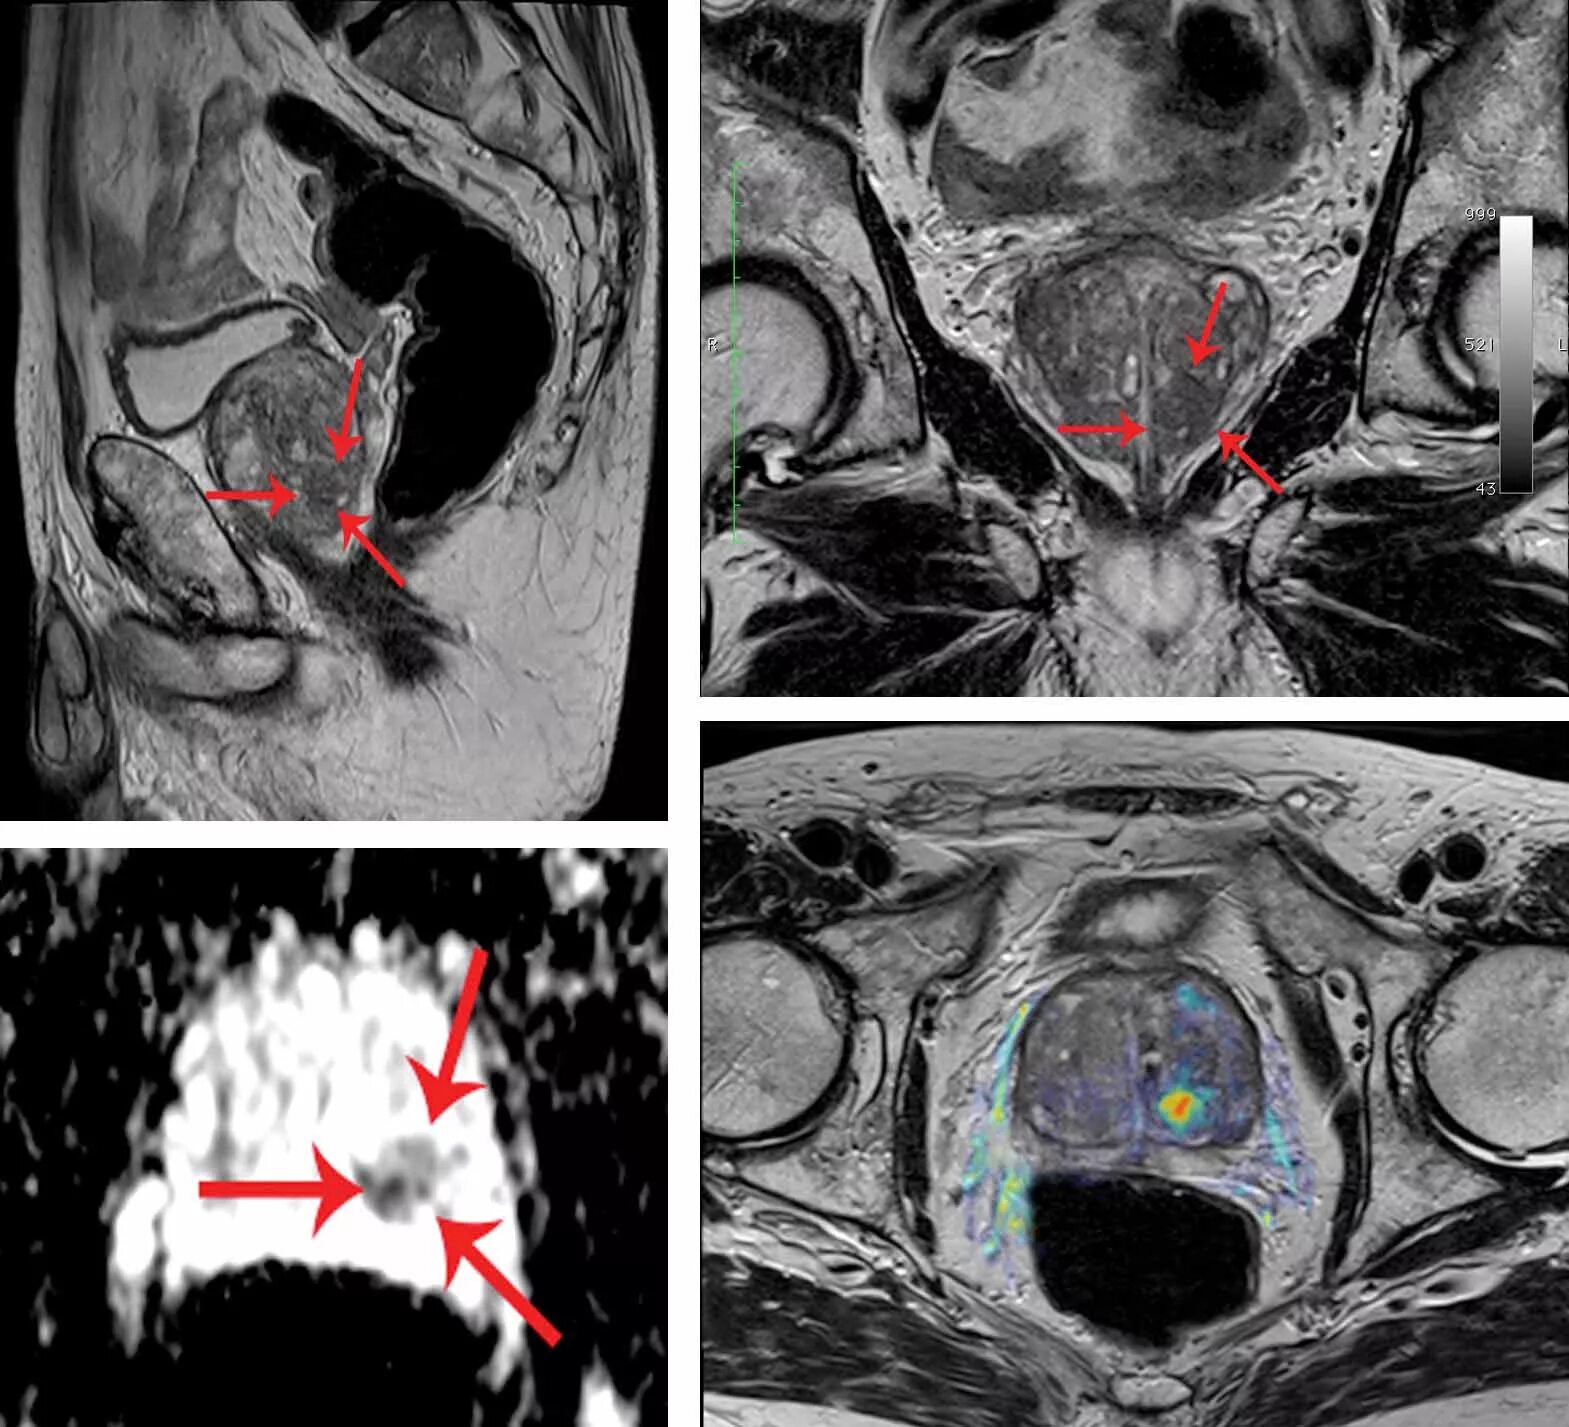

Адт при раке простаты